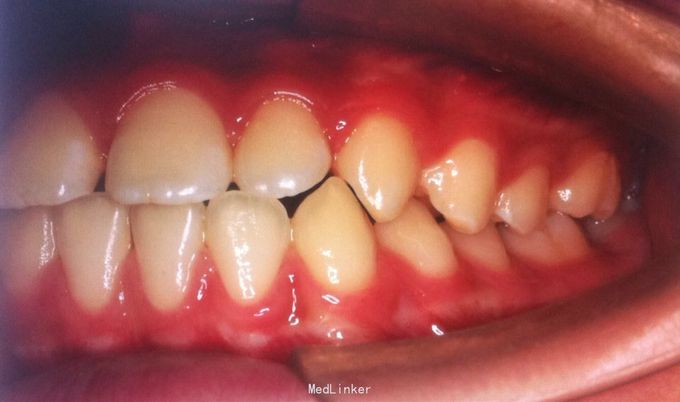

恒牙期 磨牙中性关系 前牙覆合覆盖关系正常 A1B1之间1mm间隙

安氏一类 不拔牙矫治,直丝弓矫治器,排齐整平上下牙列,关闭前牙散在间隙,矫治后磨牙中性关系,前牙正常覆合覆盖,维持现有面型